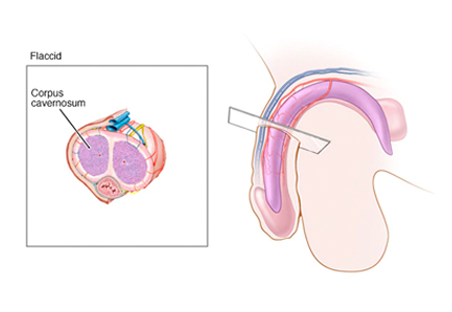

What is Erectile Dysfunction(ED)?

Erectile dysfunction(ED) is the inability to get or keep an erection firm enough to have sexual intercourse. It's sometimes referred to as impotence, although this term is now used less often.